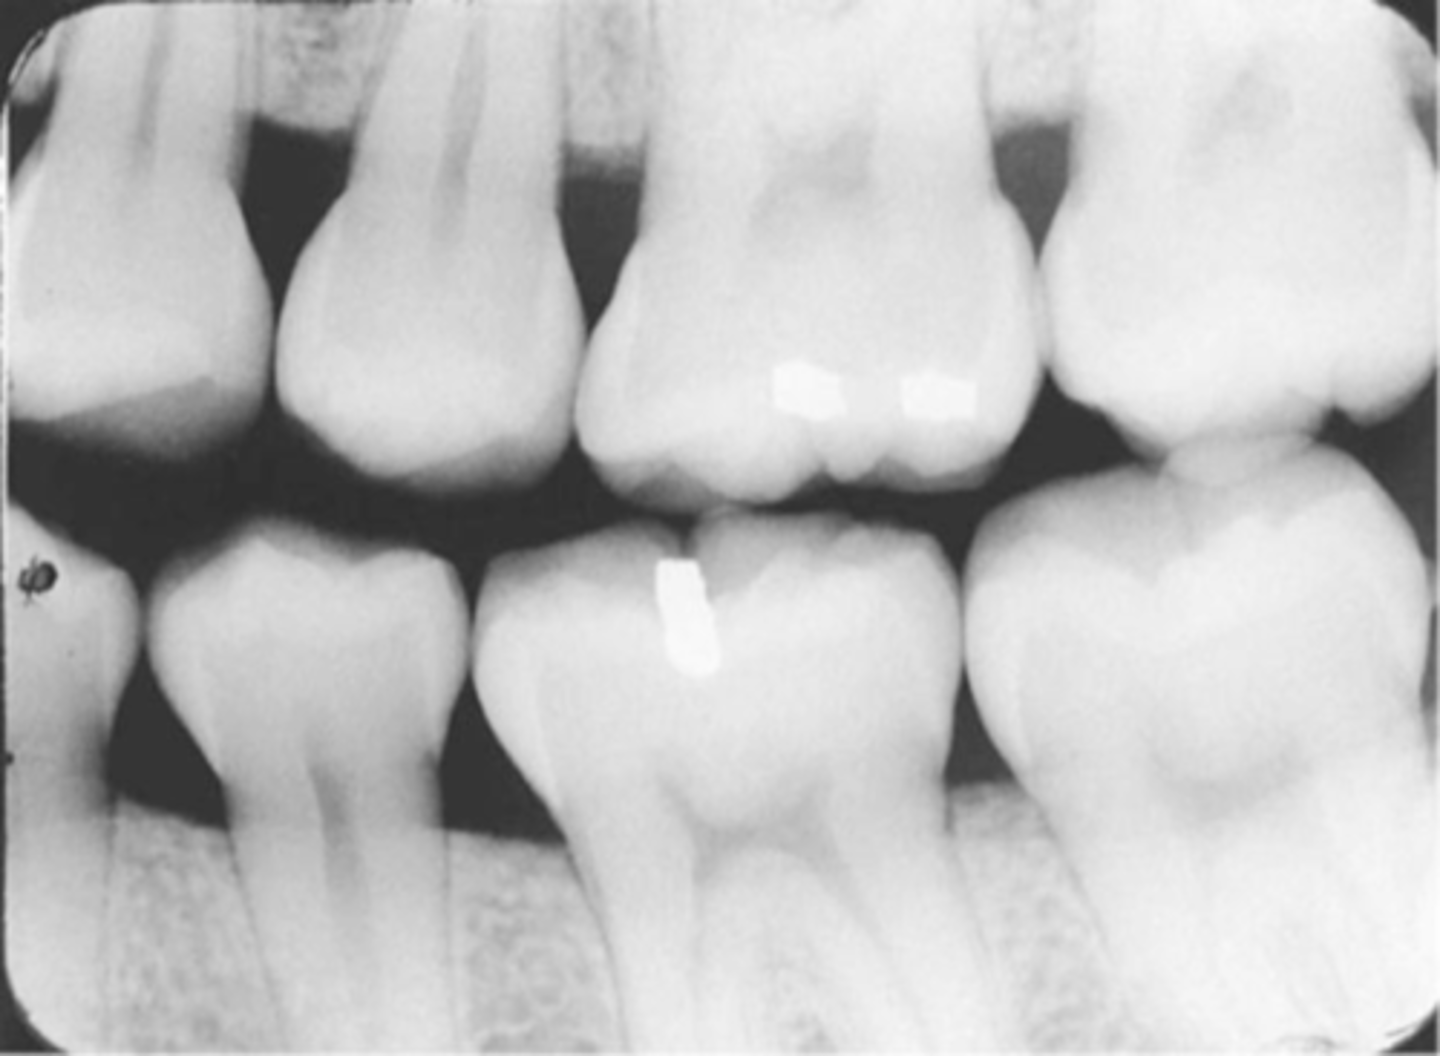

Incorrect Horizontal Angulation

-Overlapped contacts

-CR was not directed through the interproximal spaces, resulting in the proximal surfaces of adjacent teeth appear overlapped in the PA.

-Occurs in both paralleling and bisecting technique

-To prevent direct the x-ray beam through the interproximal regions

Incorrect Horizontal Angulation -->Bite-Wing

-CR was not directed through the interproximal spaces.